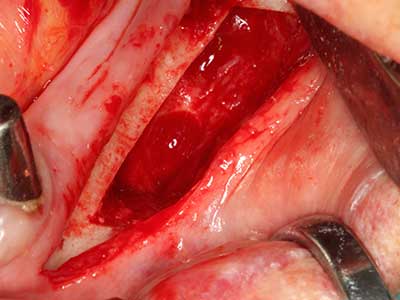

Indication: Preparation near nerves

When surgical procedures are performed on bone in the immediate vicinity of sensitive structures such as blood vessels or nerves, rotary instruments pose a significant risk of iatrogenic injury. Piezoelectric devices can be helpful for preparation of bone covers and removal of hard tissue close to nerves, particularly for exposure of nerves after iatrogenic injury but also during nerve lateralization for resective and reconstructive procedures or implant placement (Fig. 17-20). Light contact between the piezotip and the nerve does not generally result in damage but proceeding incautiously with saw-like motions or attachments where a residual bone substrate remains may cause temporary or even permanent nerve damage. However, the risk of damage is considered to be substantially lower than when using saws or milling instruments (Pereira, Gealh et al. 2014).